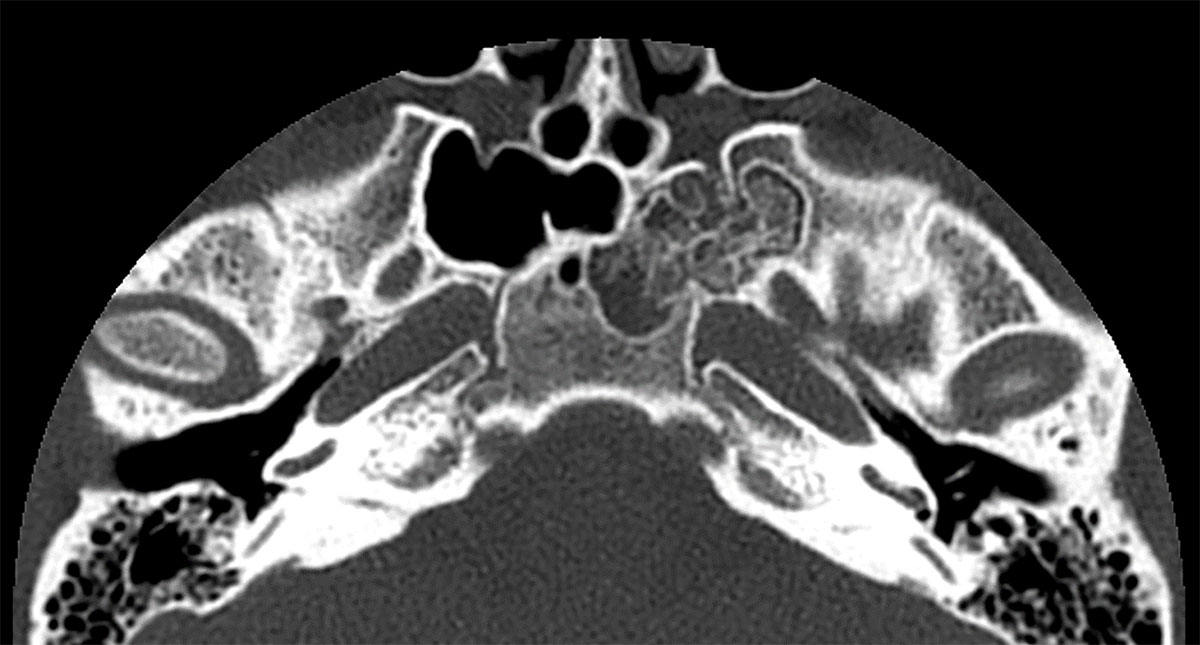

Figure 2

Arrested pneumatization of the sphenoid. This frequently encountered congenital variant of the skull base is demonstrated on this axial CT image in bone window settings. It should be recognized as a benign entity without clinical significance that does not require further follow-up.